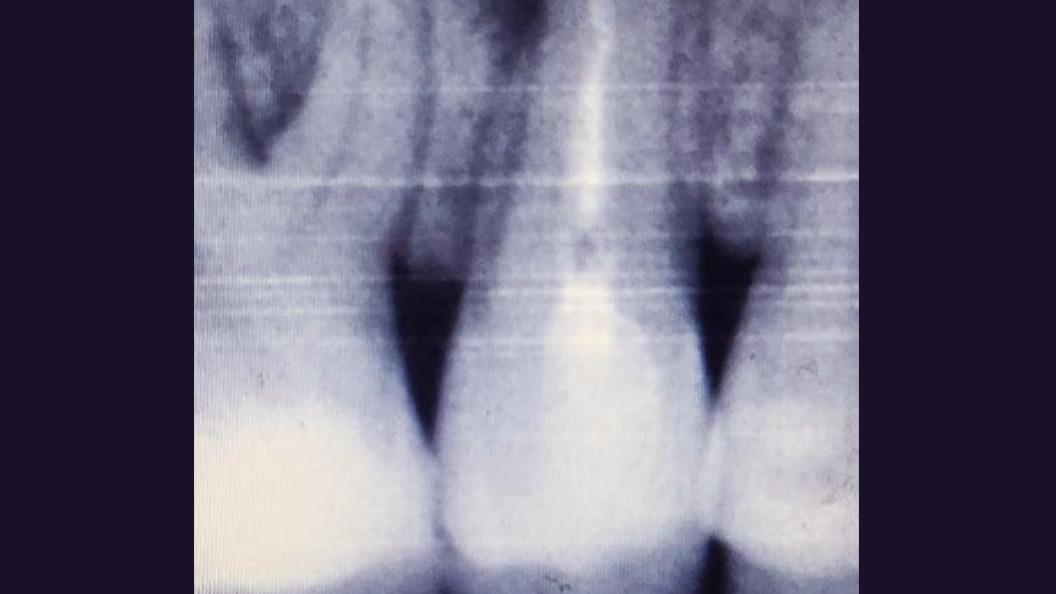

До и после лечения

В клинику обратился пациент с жалобами на постоянные ноющие боли и резкую боль при накусывании. С его слов, зуб ранее лечили в другом ЛПУ по поводу хронического фиброзного пульпита. После осмотра врач Черных Антон Алексеевич проанализировал рентгенограмму, поставил диагноз и провёл повторное эндодонтическое лечение зуба 1.5.

Перелечивание каналов необходимо при воспалении тканей, окружающих зуб. Требуется при попадании инфекции или при дефектах ранее проведённого лечения: недопломбированные участки, рассосавшийся пломбировочный материал внутри каналов.

В ходе лечения были проведены следующие работы:

- эндодонтическое лечение с применением коффердама

- постоянная пломбировка корневых каналов

- восстановление коронковой части зуба